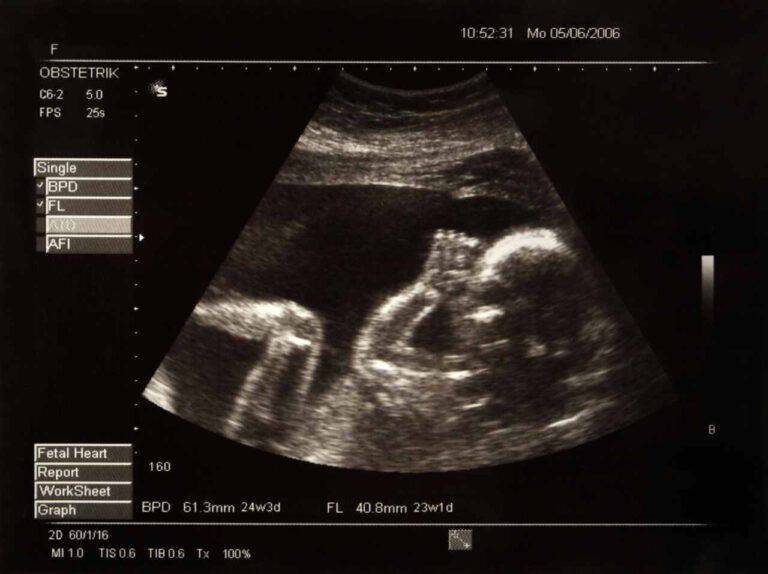

WebSalve , ho 40 anni. riporto un esito di mammografia con scritto mammelle a struttura fibroghiandolare.. presenza al qse di destra di radiopacità a margini non ben definiti del. Web« introduzione: l'ecografia e gli ultrasuoni. Modalità di applicazione degli ultrasuoni alla diagnostica: Eco di superficie: si usano sonde ad alta frequenza (7,5-15. WebLe lesioni ipoecogenee sono la rappresentazione ecografica più comune di un’infiammazione. Quello ad essere rilevato è infatti l’edema dei tessuti che riduce. WebRuolo dell'ecografia con mezzo di contrasto (CEUS) come problem-solving nella valutazione delle piccole masse renali (SRMs) indeterminate allo studio TC-RM WebL’esame è stato eseguito a digiuno con tecnica PET/TAC 60 minuti dopo la somministrazione endovenosa di 18F-FDG. sono state acquisite immagini della. Webil fegato e' di dimensioni modicamente aumentate ad ecostruttura addensata come da steartosi, in cui si rileva in S6 la presenza di una formazione nodulare,. WebL’ecografia ostetrica è oggi parte integrante del percorso di sorveglianza diagnostica della gravidanza e rappresenta per ogni donna uno dei momenti più. WebFra i qsuperiori di destra in sede profonda di segnala formazione oavalare a margini netti di 18 per 6mm (lunghezza per spessore) priva di evidente aumento di segnale, all'Ecd, di. WebL’ecografia intestinale nella diagnosi di morbo di Crohn In ambito chirurgico l’utilità dell’ecografia nella diagno-si di malattia di Crohn si pone fondamentalmente in due.

Argomenti Ecografia in gravidanza: nell'immagine compare il volto del bisnonno virale